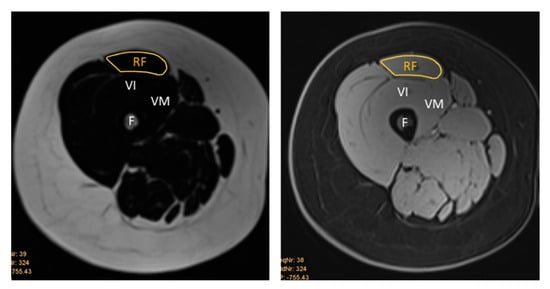

The MR images were qualitatively analysed using the institution’s picture archiving and communication system (PACS). The same anatomical landmarks were used as for the US images. For the RF muscle, this was midway between the anterior and superior iliac spine and the superior aspect of the patella. For the BB muscle, the ROI was two-thirds of the way between the acromion and the antecubital crease. The MRI measurements were obtained by manually tracing the cross-sectional boundary of the right RF and right BB, as shown in Figure 3 and Figure 4. The boundary segmentation measurement was copied from the water image to the fat image, so the CSA had the exact same size. Using the axial water and fat images of the RF and BB muscles, the MR %FF was calculated using the following formula: MR %FF = (signal-fat/[signal-water + signal-fat] × 100) [27]. Each operator then segmented magnetic resonance images, which a senior doctor with more than ten years of experience then reviewed.

Figure 3. Representative T1-weighted Dixon VIBE MR image tracing the cross-sectional area of the right RF on the fat-based image (left) and water-based image (right). RF = rectus femoris, VI = vastus intermedius, VM = vastus medialis, F = femur.